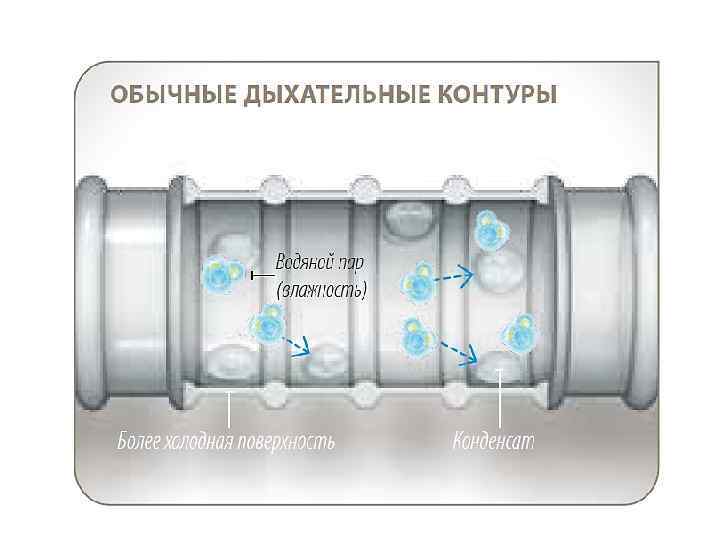

Конденсат шлангах

Конденсат шлангах

Конденсат шлангах

Конденсат шлангах

В шлангах тэн

В шлангах тэн

Тен под держ в конт уре защи ивает тем щае тера т от туру конд и енса ции

Тен под держ в конт уре защи ивает тем щае тера т от туру конд и енса ции